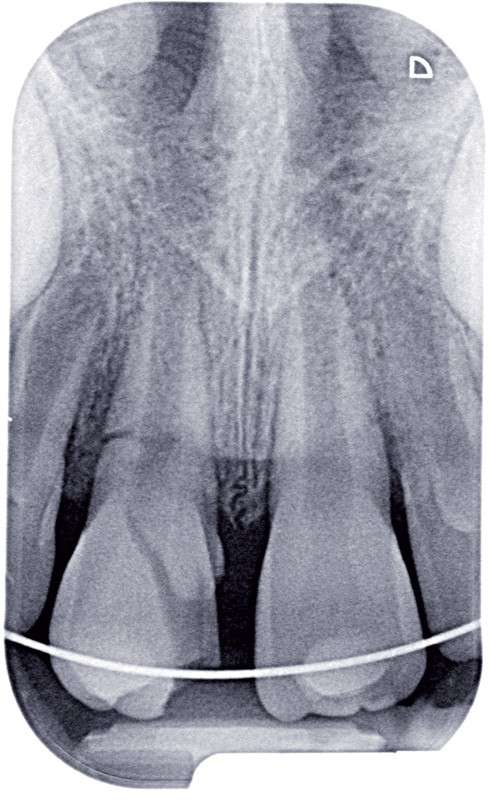

a à d Jeune patiente âgée de 8 ans, adressée suite à un traumatisme survenu 3 semaines auparavant, pour l’extraction de sa 21. La vue clinique montre un saignement ligamentaire, une mobilité coronaire et une fracture coronaire amélodentinaire longitudinale partant de l’angle mésial et se poursuivant en direction radiculaire sous-gingivale (a). Un test de vitalité positif indique que la dent est vitale, la radiographie permet de poser le diagnostic de fracture coronoradiculaire, et d’objectiver l’immaturité radiculaire (stade 8 de Nolla) (b). Une contention est mise en place et la plaie dentinaire coronaire est scellée au mieux par collage afin de limiter le risque d’une complication infectieuse (c). A 15 jours la dent est vivante et aucune complication n’est apparue (d). La patiente est revue après 3 mois pour déposer la contention, le test de vitalité est positif, et la radiographie de contrôle montre une apexogenèse en cours (e). Cependant la gencive s’est invaginée dans le trait de fracture (f). La zone est débridée sous microscope (g) puis scellée et reconstituée à l’aide d’un adhésif SAM et d’un composite fluide (h). Le contrôle radiographique à 6 mois est satisfaisant (i). Ce cas clinique illustre le fort potentiel des pulpes jeunes et du ligament alvéolodentaire à résister aux agressions et à assurer les fonctions dentinogénétiques et l’édification radiculaire.